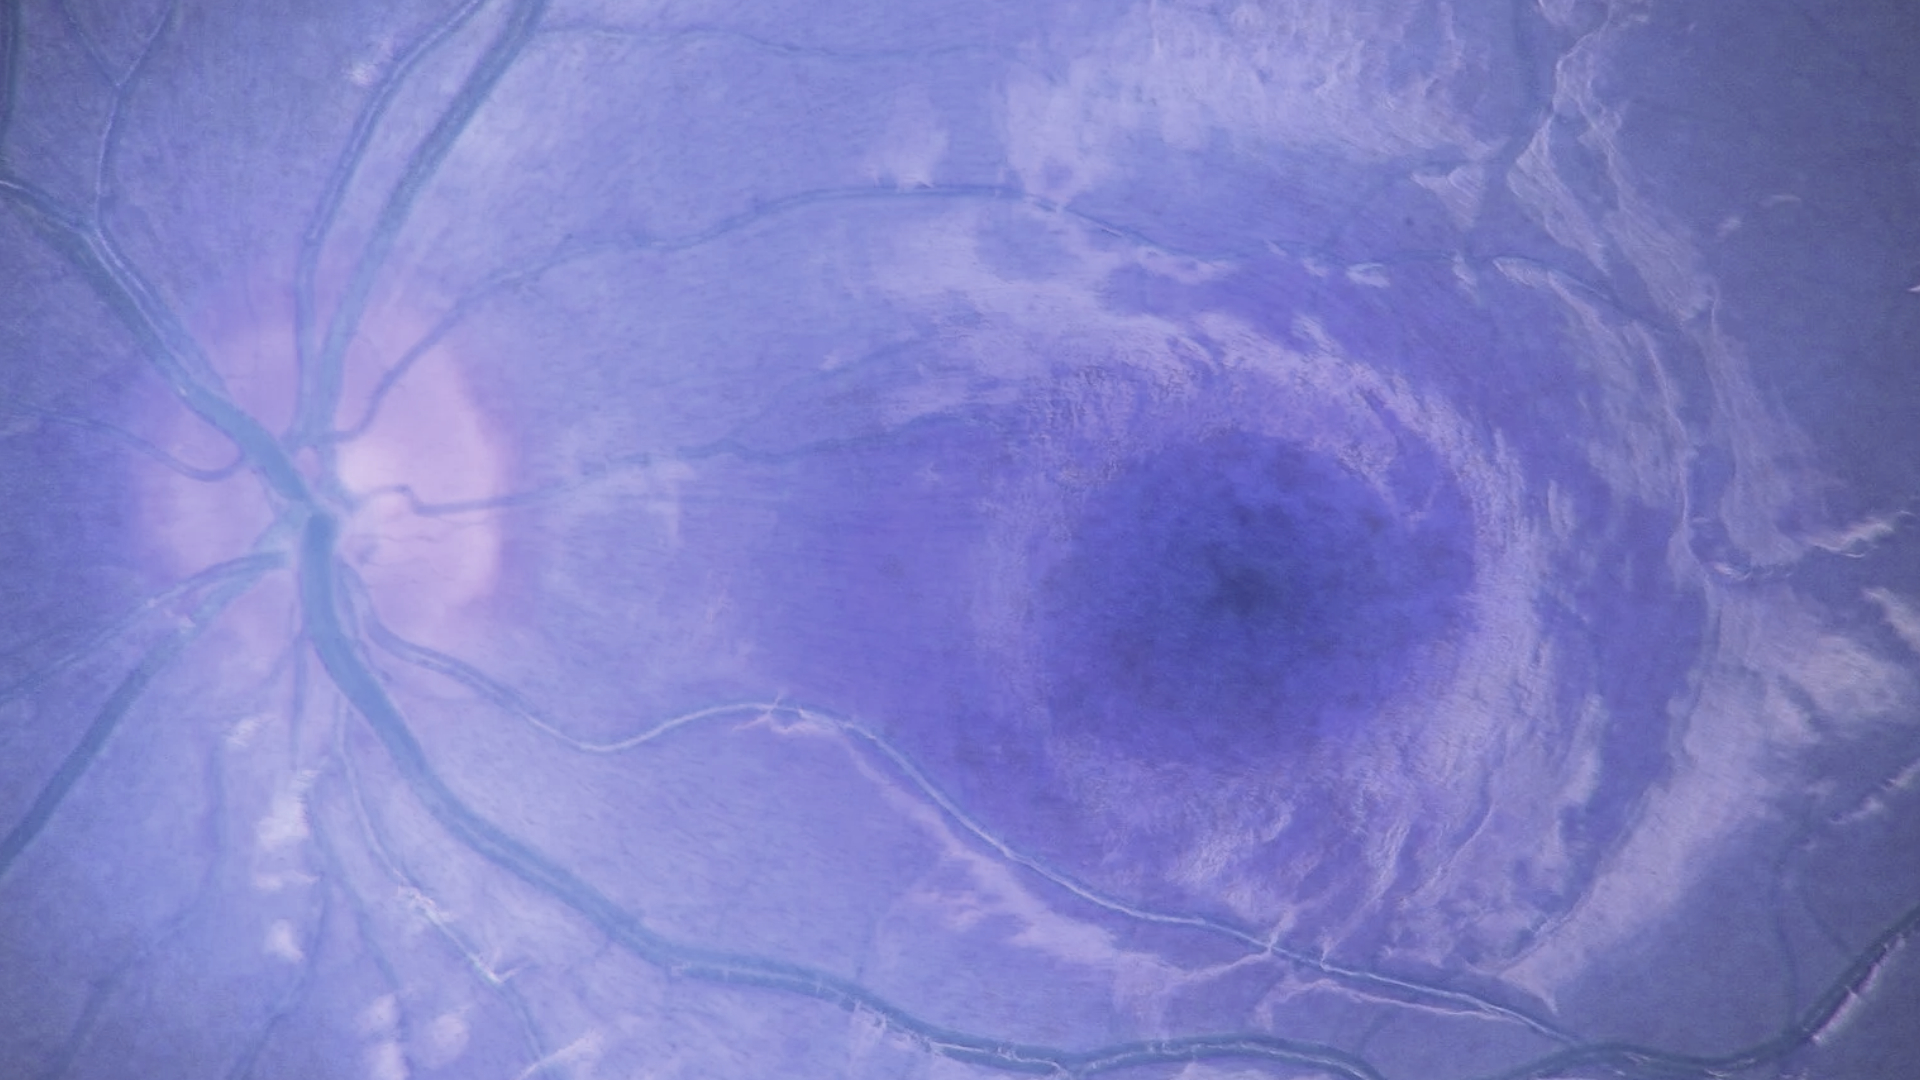

Sarı Nokta Hastalığı

Retina Hastalıkları

En Çok Görülen 5 Retinal Hastalık